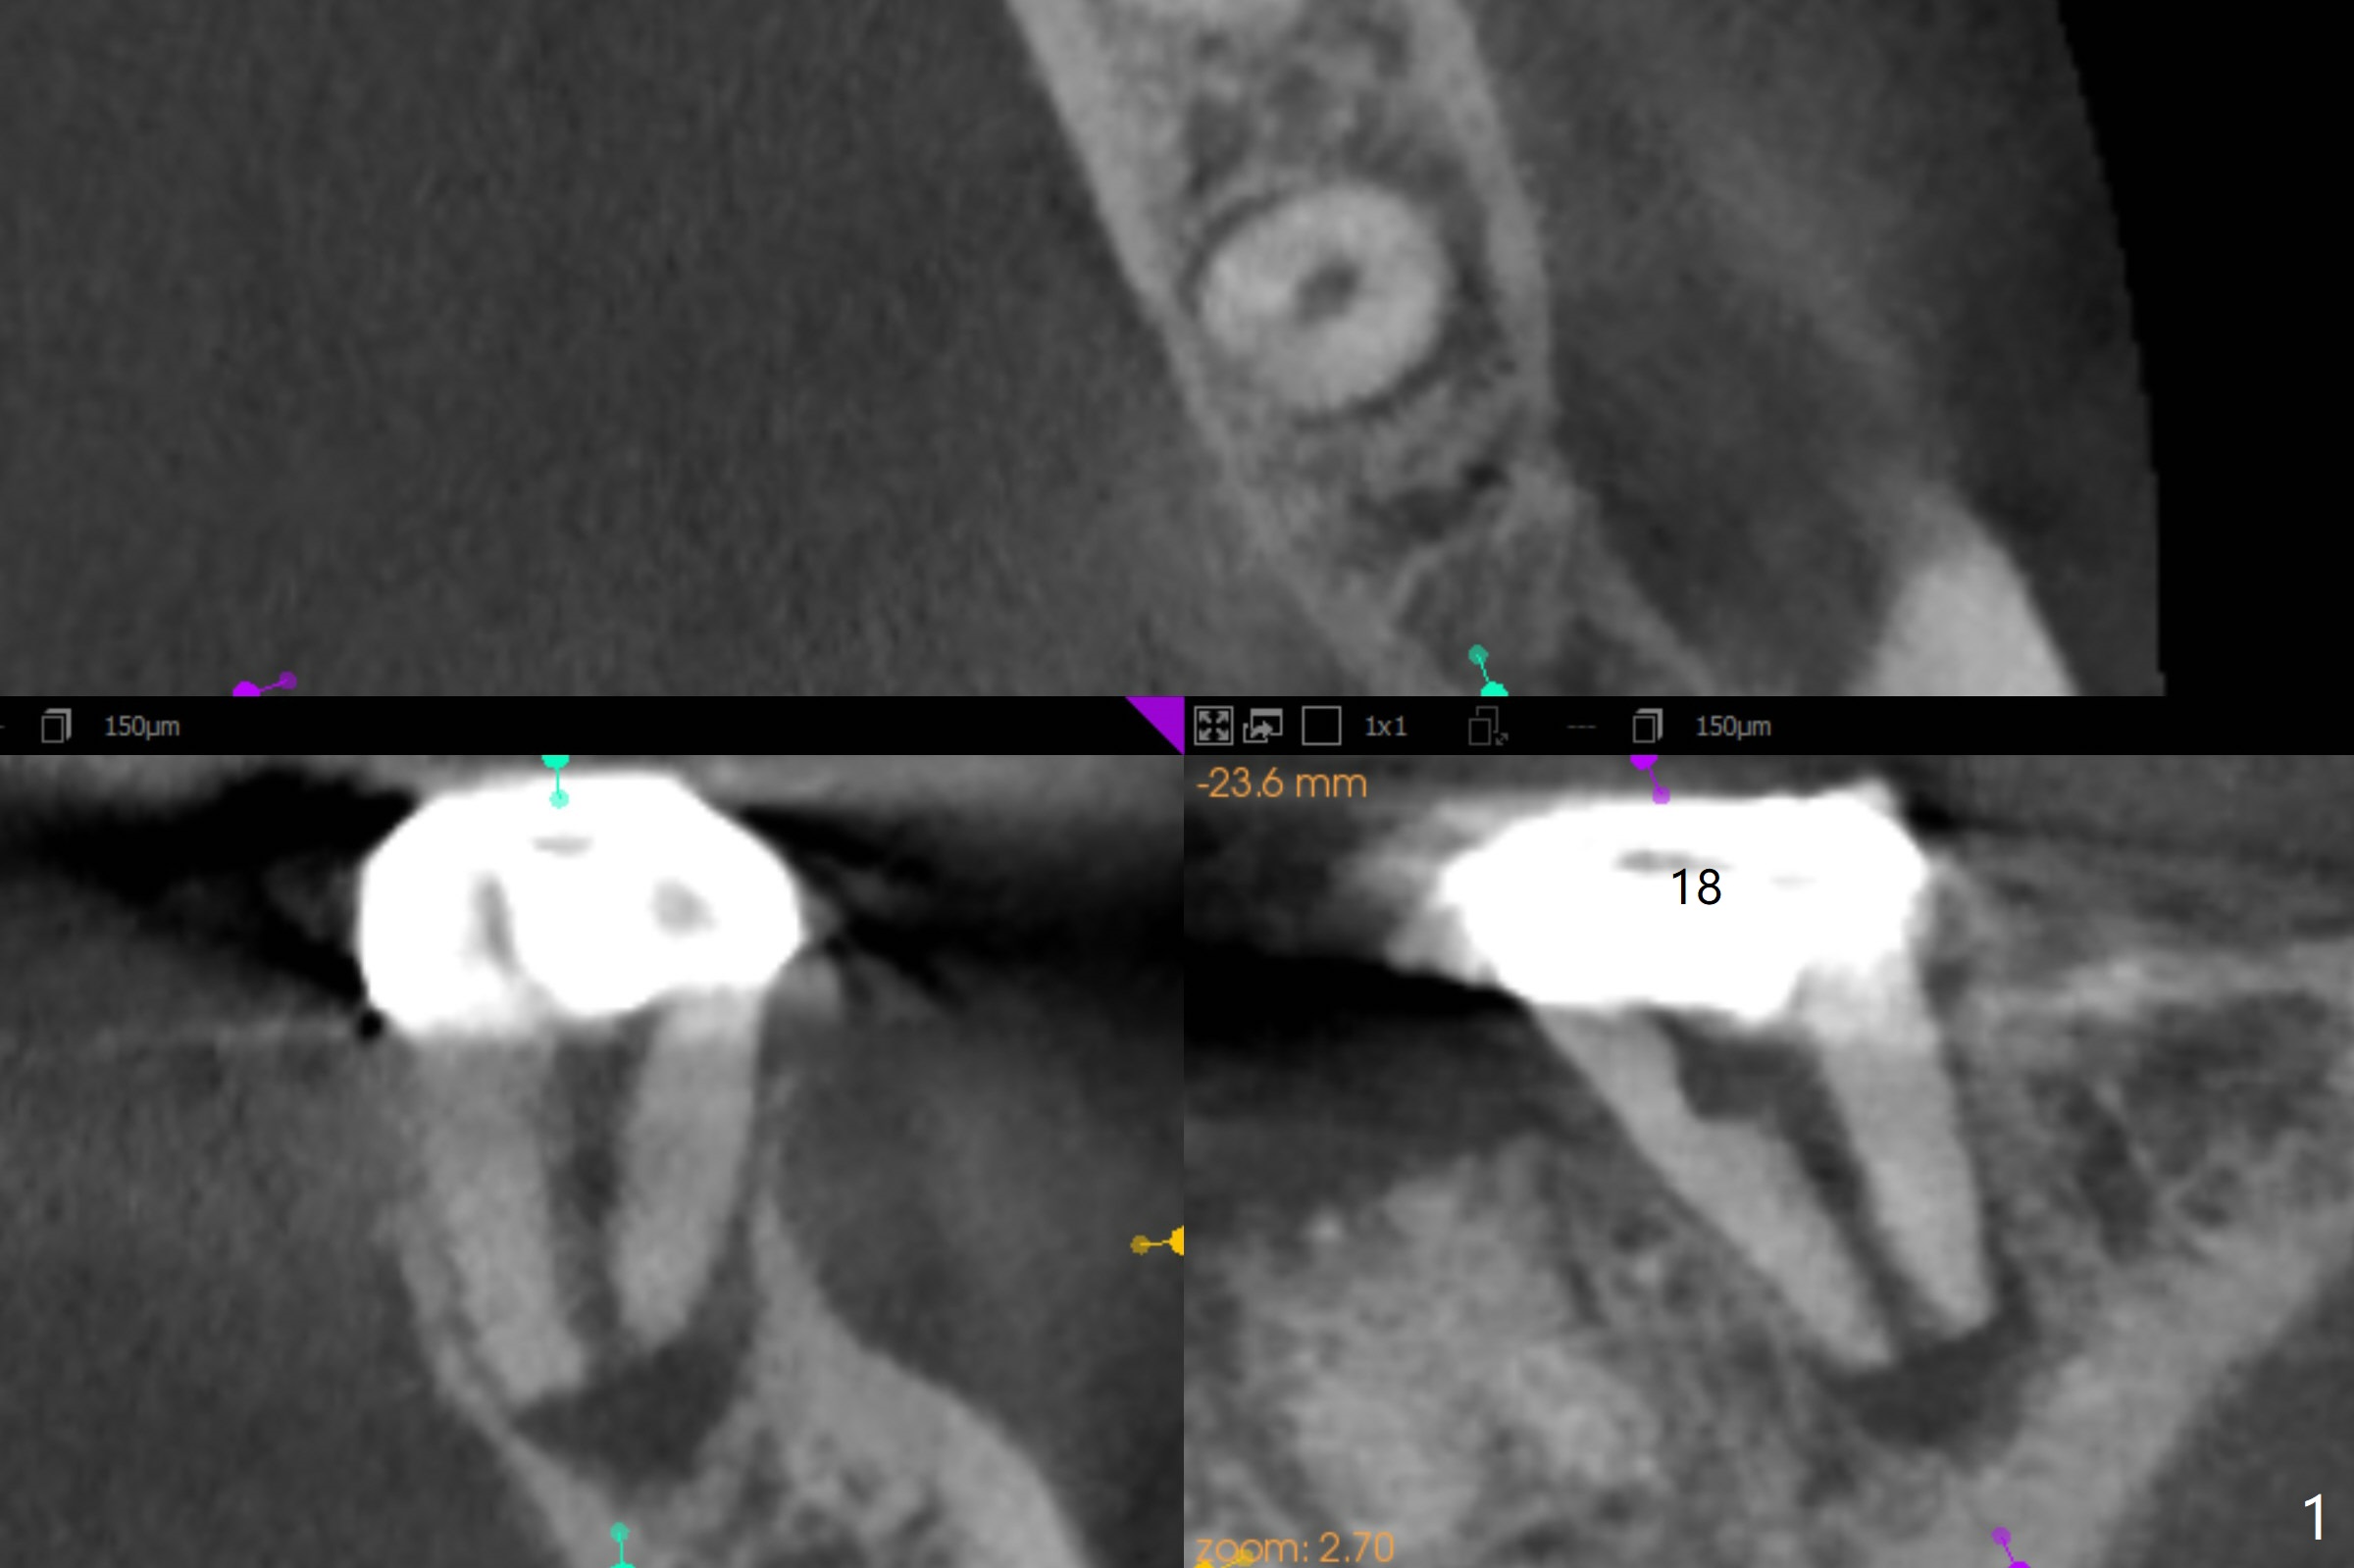

A 54-year-old woman will return for #18 extraction and implant 1 or 2 years post implants at #19 and #30. In fact the tooth has had incomplete RCT with PARL. Reanalysis of CT taken on 02/02/2017 (before RCT) shows that RCT retreatment should not be too difficult (Fig.1,2). If the treatment turns out to be not successful, a 5x10 mm immediate implant will be done with a possible 25 degree angled abutment (Fig.3,4).